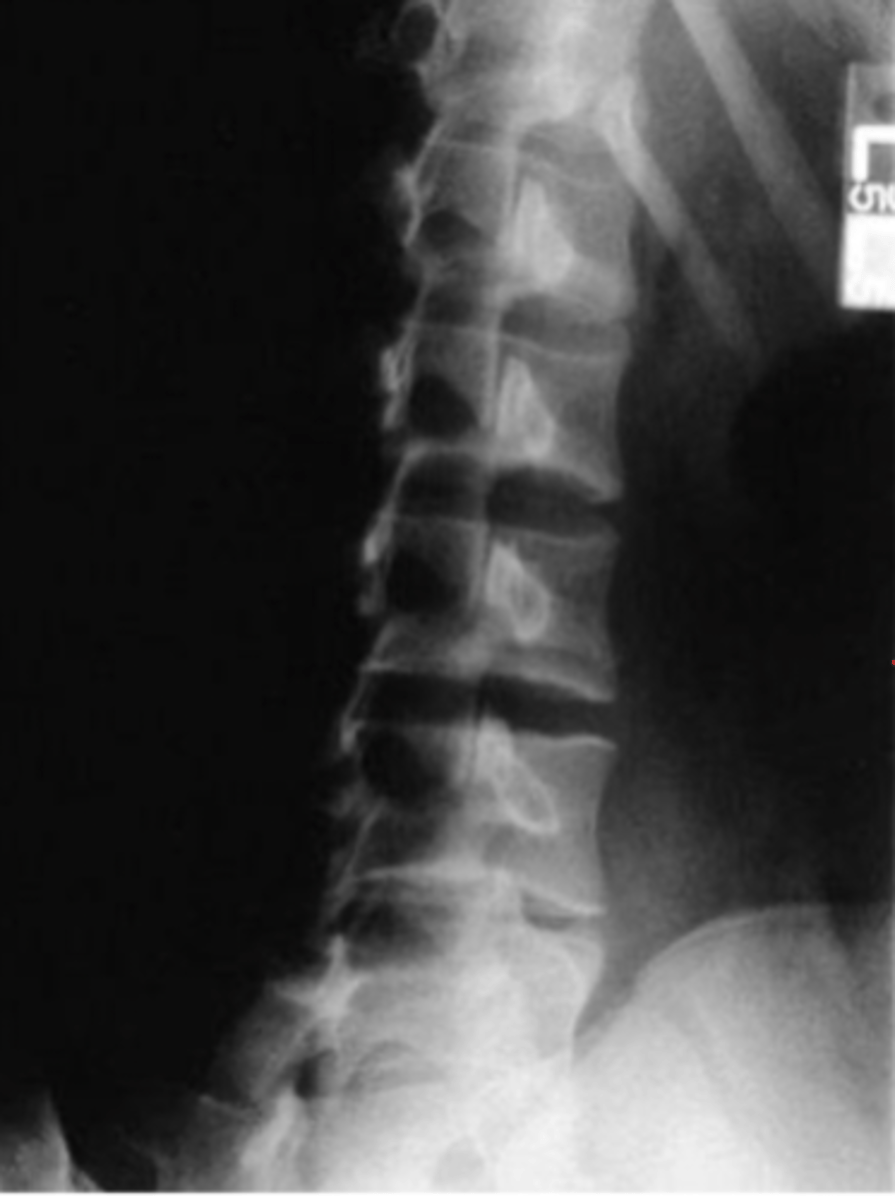

Oblique Lspine

What view is this?